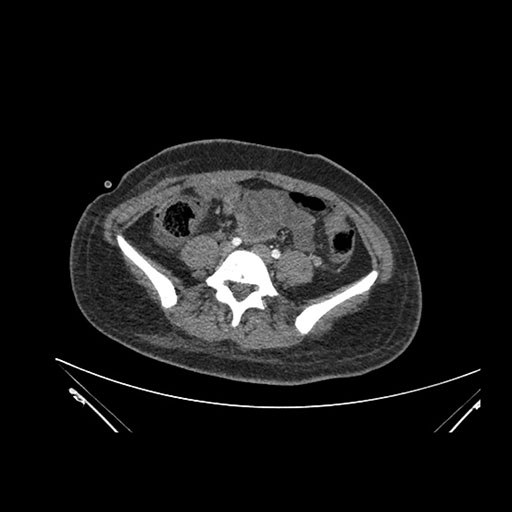

Axial Arterial

Axial Venous